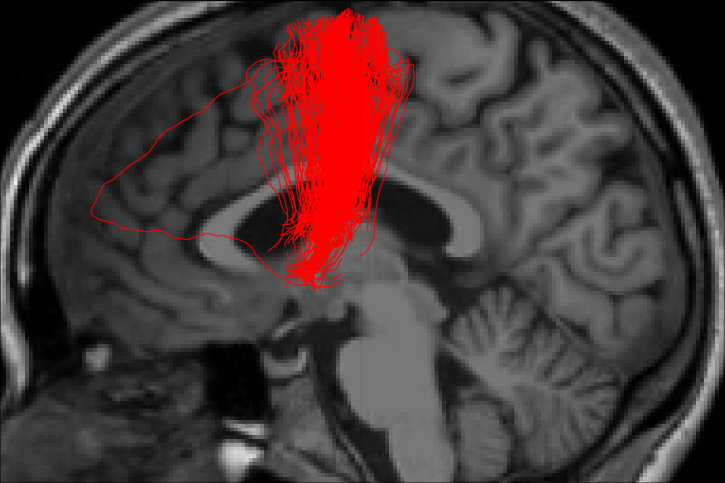

- TractFiltering (Cousineau et al 2016. ISMRM, Coté et al 2015. ISMRM)

- Tractometry (Cousineau et al 2016. ISMRM)

FA

NUFO

Metrics

- Mean value per bundle

- Mean value per point

- Profile

- Volume

Project: Catherine Vien, Julien Doyon

-----------------

REAL LIFE